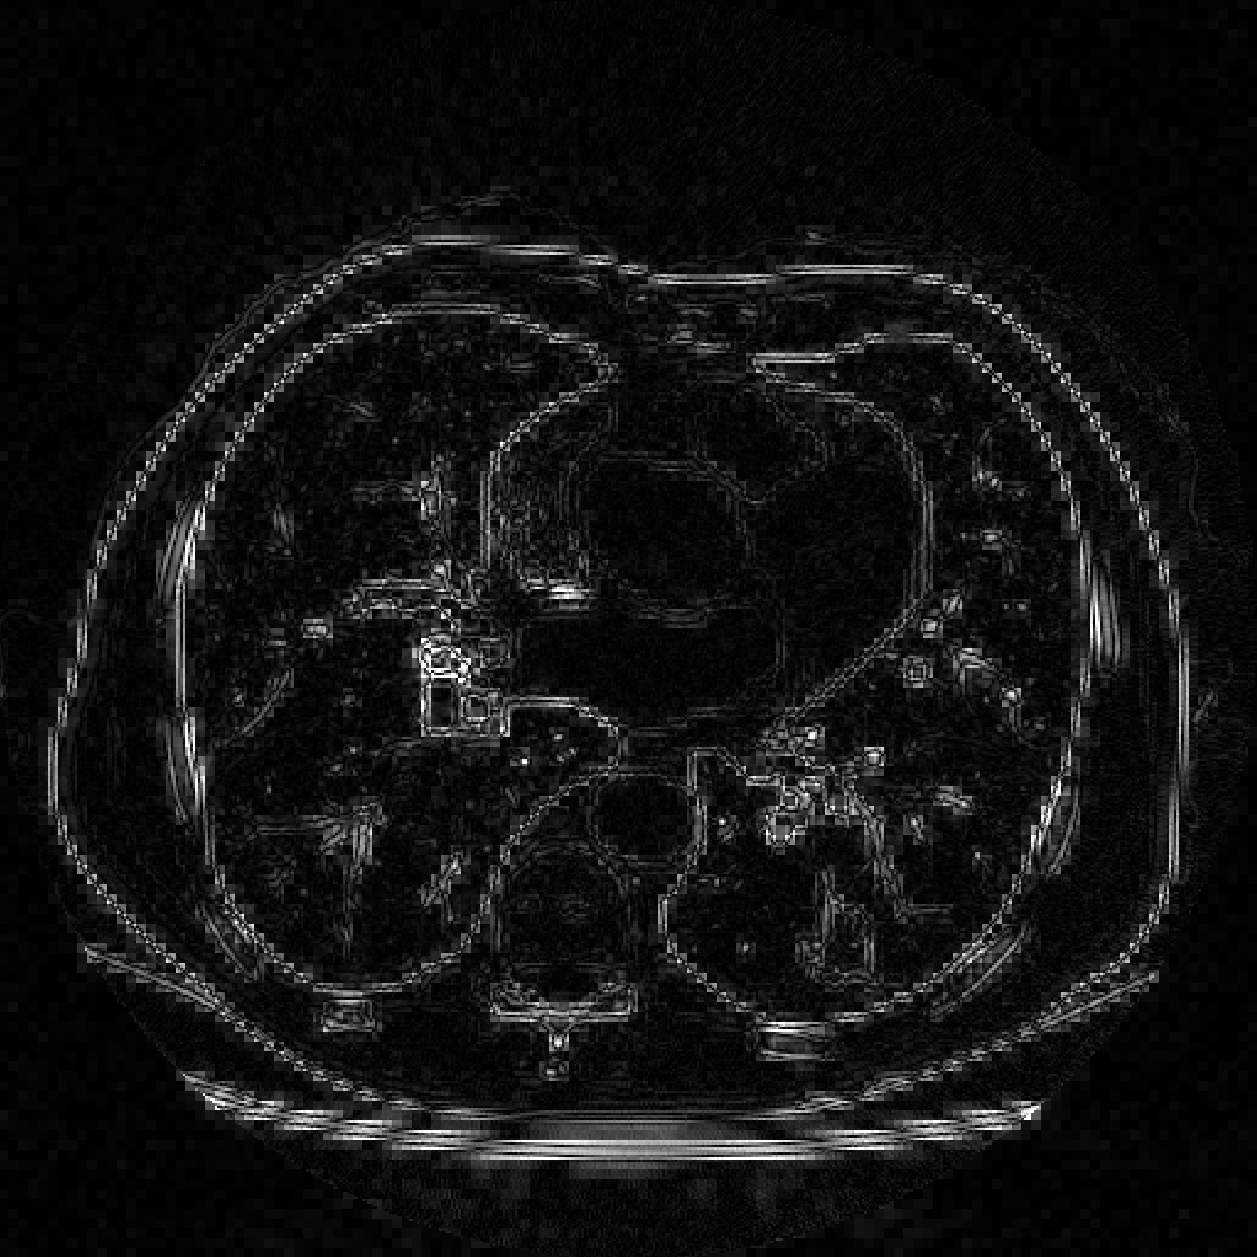

We compare the computation time and SNR of back projection among oblique method, orthogonal method under band limited assumption and box spline methods. We throughly test the performance of oblique method, box spline methods and blurred box spline method (box spline method with detector blur effect). Three images are used in our experiments, the first one consists of randomly placed ellipses, the second one is Forbild head phantom, and the last one is a real CT image from LIDC-IDRI dataset [13] (Fig.2). In our experiments, we fix the sampling steps to be equal in all dimensions, and , where is the downsampling rate. The number of views is set to . Signal to noise ratio (SNR) in dB and structural similarity index (SSIM) are measured for all the methods. All computations were done on one PC (Windows 10 with a 3.7GHz 6-Core Intel Core i7-8700K processors and 32GB of RAM) using Matlab.

(a)

(b)

(c)

Fig.4 shows that our methods provide an improvement over the oblique method in our test cases. Fig.5 shows that our methods are more consistent when the resolution is relatively low. The reason is that oblique method truncates and estimates the sinc function, while we calculate the box spline exactly and have more accurate back projection. Fig.6 shows the absolute total error of the real CT image, the image reconstructed by oblique method suffers from higher error.